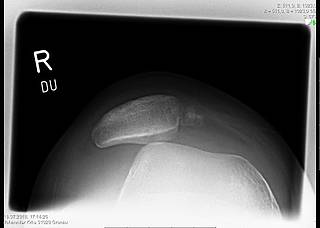

MPFL demolition and trochlear dysplasia

In surgical interventions, the so-called MPFL (medial patellofemoral ligament) is the focus of treatment, because it is the main stabiliser of the patella (kneecap) in flexion degrees close to extension and works against a large part of the outward forces. This ligament is torn in about 90% of cases after a patellar dislocation. During the operation, it is replaced by a tendon from the patient's own body (gracilis or quadriceps tendon), which is tensioned in the course of the MPFL. If there are other factors that promote instability, these are also included in the therapy. For example, it may be necessary to create a new sliding groove in the femur for the kneecap in order to achieve bony stability.